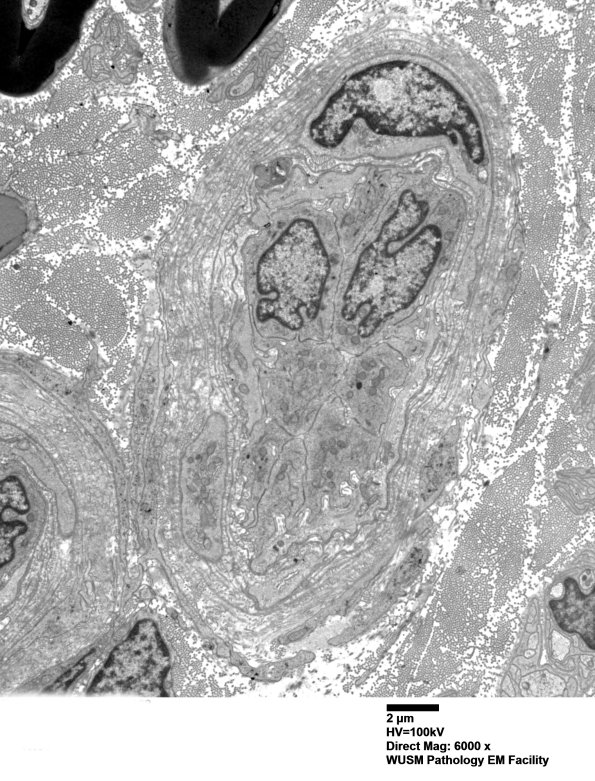

Washington University Experience | VASCULAR | Hypoxia-Ischemia, fetal-neonatal | White Matter | 15B1 (Case 15) HIEM EM 002 - Copy

15B1 (Case 15) HIEM EM 002 - Copy